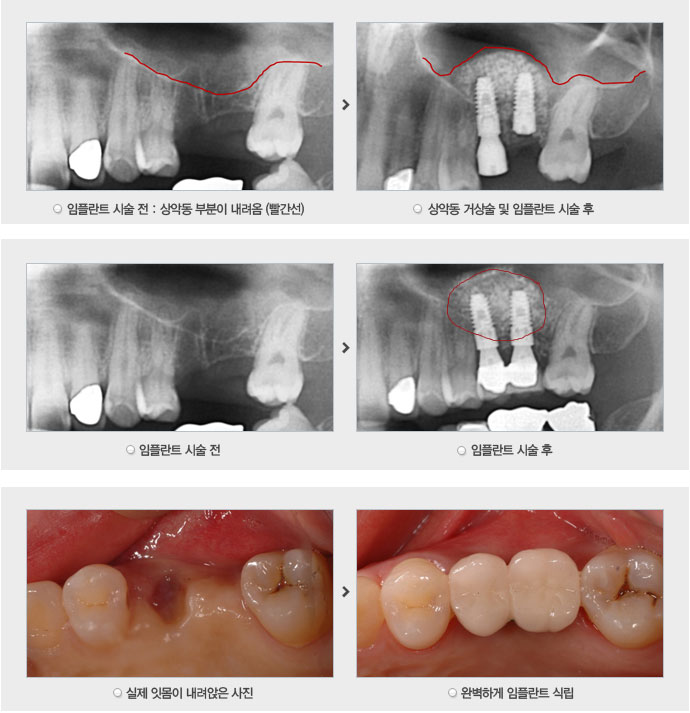

치료증례

저희 의원은 환자의 동의를 얻은 사진만 기재됩니다.

위 어금니 발치 후 변화